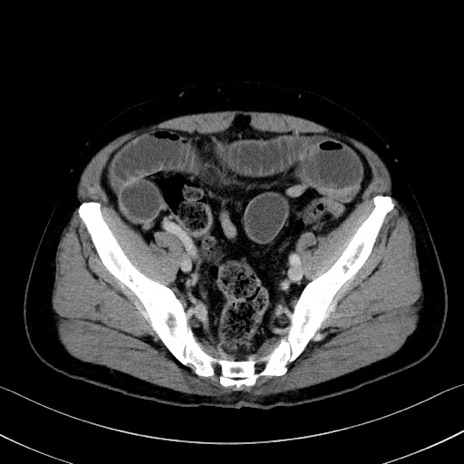

症例35(横断像)

【症例】70歳代 男性

【主訴】腹部膨満、嘔吐

【現病歴】昨日より腹部膨満感出現。本日増悪し、仙痛出現。嘔吐あり、受診。

【既往歴】糖尿病、胆摘後

【身体所見】BP 149/80mmHg、HR 74/min、BT 35.9℃、腹部:膨満、軟、圧痛なし。腸雑音減弱あり。上腹部正中切開瘢痕あり。

【データ】WBC 13500、CRP 1.72